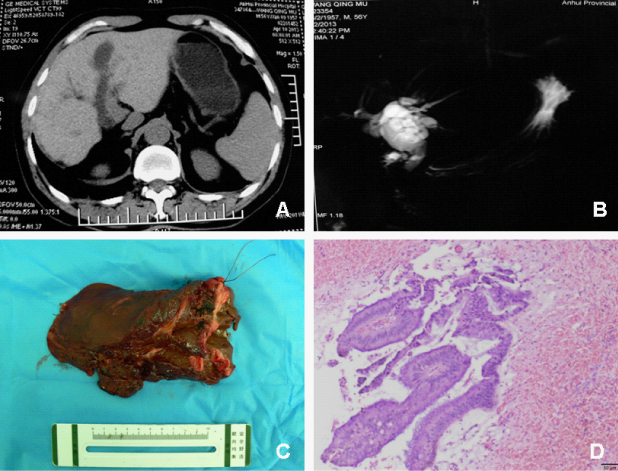

A 56-year-old man was admitted to our hospital in April 2013 with a 2-year history of recurrent episodes of abdominal pain. He had a previous surgery history of cholecystectomy, common bile duct exploration and T tube drainage due to its own disease of cholelithiasis. Physical examination revealed definite tenderness in the right hypochondrium only. Laboratory tests detected a total bilirubin of 22.6µmol/L (normal range, 3.4-20.5µmol/L), direct bilirubin of 14.2µmol/L (normal range, 0.0-6.8µmol/L), ALT of 24IU/L (normal range <60 IU/L), AST of 19IU/L (normal range <60IU/L), ALP of 75 IU/L (normal range, 40-150IU/L), gamma GTP of 52IU/L (normal range, 4-87IU/L). Tumor markers (CEA, CA19-9, a-FP) were normal. Computed tomography (CT), abdominal ultrasound demonstrated intra hepatic duct dilatation localized to the left lobe with a markedly dilated common bile duct, and floccules in left intra hepatic duct. MRCP revealed dilated intra hepatic ducts and common bile duct, within multiple irregular filling defects inside the distal common bile duct. Intraoperative Choledochoscopy demonstrated a dilated (1.5cm diameter) bile duct filled with papillary, friable tissue located in left intra hepatic ducts. A decision was made to proceed with left lateral lobectomy of liver, which would have required a left hepatectomy (for which the patient had not given consent). A per cutaneous T-tube was left within the bile duct. Histopathological examination demonstrated papillary lesion characterized by fibro vascular core with overlying mucin-producing columnar epithelial cells dysplasia (Grade 2) (Figure 1). Immunohistochemical markers, cytokeratin (CK) 7 (±), CK 20 (-), CEA (-), Ki-67 (+) 20%, p53 (-), alpha1-antichymotrypsin (ACT) (-). After 7 months of follow-up, there was no recurrence.

Figure 1 Imagings of the patient. (A) Computed tomography (CT) showed cyst-like dilatation of left lobe of bile duct. (B) Magnetic resonance cholangiopancreatography (MRCP) showed dilatate intra hepatic bile within multiple irregular filling defects inside the common bile duct. (C) Surgical specimen showed papillary fragile mass with gelatinous mucin-producing. Post-operative pathology demonstrated dysplasia of biliary epithelia, exerting as papillary (HE χ100).